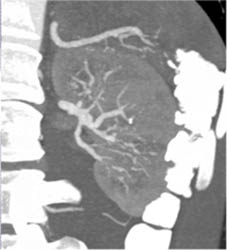

Superior Mesenteric Vein (SMV) Aneurysm